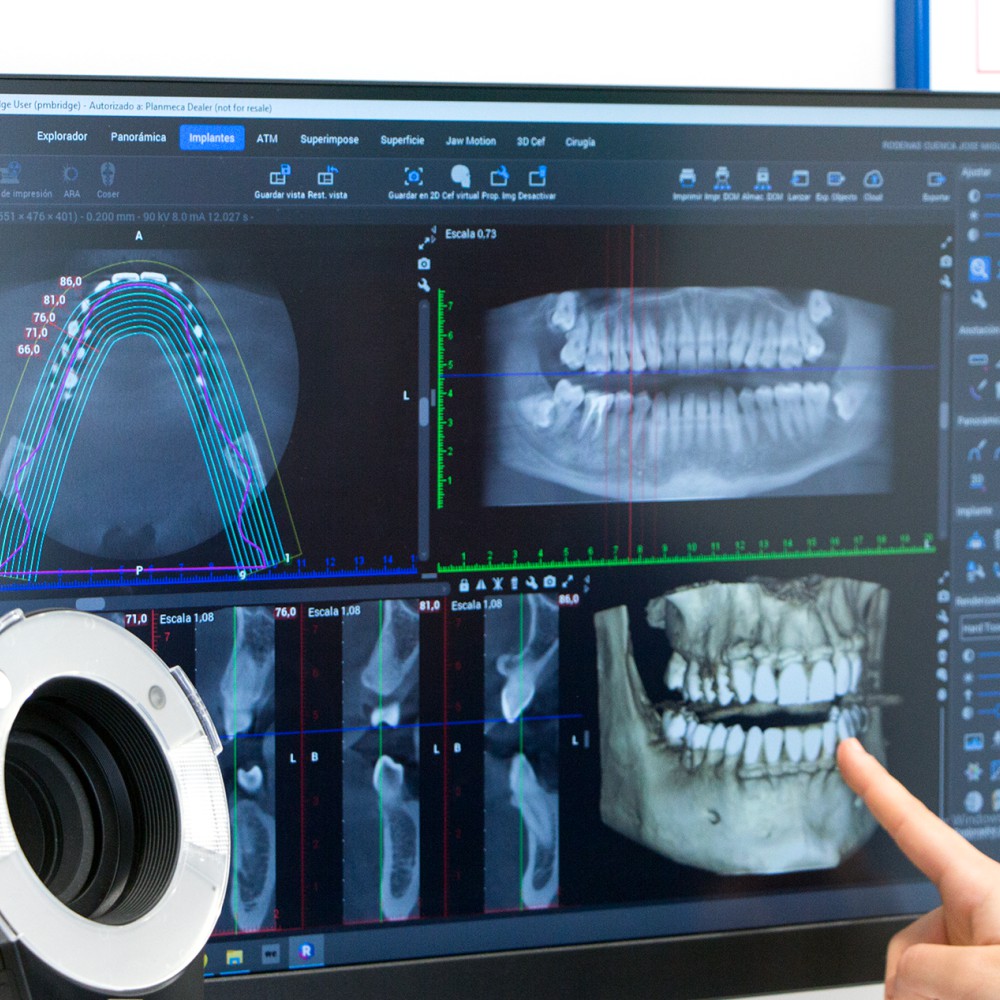

Estudiamos la viabilidad

Antes de hablar del tratamiento estudiamos bien tu caso con pruebas digitales detalladas para saber exactamente cómo está tu boca y cuál es la mejor opción en tu caso.

Diagnósticos Complejos

Dedicamos el tiempo y las pruebas necesarias para entender tu situación al completo y ofrecerte un diagnóstico claro.

Diagnóstico y Escáner 3D

Realizado por el Dr. Company o la Dra. Chuliá. Te entregamos un plan de tratamiento completo y digitalizado, sin compromisos.

Planificación Digital

Analizamos tu caso en software 3D antes de tocarte. Diseñamos la posición exacta de cada implante o carilla para garantizar la estética y función perfectas.